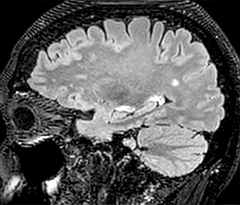

In this example, the optional 3D multishot susceptibility weighted sequence with 0.6 mm isotropic voxels is 2 lesions with a central vein sign (arrows) and one lesion with a phase-rim sign (arrowhead). The total scan time, including SmartBrain and axial PD/T2 3mm, is 11:10 min. and is 18:30 min. with the optional 3D PSIR and 3D SWI multishot included.

“We used to have long examination times for certain types of patients, a few lasting more than 40 minutes,” says Dr. Savatovsky. “What is remarkable, is that now all these examinations are below 30 minutes, which opens up opportunity to add more sequences when needed. It’s really hard to keep a patient for more than 40 minutes in the scanner, but because we have now cut scan times by at least 10 minutes, we can add more sequences without making the exam too long. And this is where the new system helps us make a difference. Examples include our examinations for informing brain tumor classification or giant cell arteritis workup, or for intracranial wall imaging – so in patients where we need several advanced sequences or high resolution sequences.” “We added three additional sequences in our brain neoplasm classification exam: a 3D SWI sequence, APT and ASL on top of 3D morphologic sequences, an isotropic DSC (dynamic susceptibility contrast) and multivoxel spectroscopy. I think that in patients that need a classification for brain mass, for example, we can provide a more detailed and confident diagnosis than before, allowing the clinicians to decide for either a medical workup if no tumor is suspected, or for neurosurgery as soon as possible if a neoplasm is suspected.” “In multiple sclerosis patients, we increasingly include a multishot susceptibility sequence [3] in our routine cases, thanks to the shorter scan times. Our abbreviated MS protocol for brain is around 8 to 9 minutes, so we can ask for one or two additional sequences to visualize the central veins, or to get an additional contrast to better depict posterior fossa lesions. In cases of white matter lesions of unknown significance on FLAIR images, for example when we see high signal hyperintensities in the brain, we can add on more advanced sequences such as PSIR (phase sensitive inversion recovery) or susceptibility-weighted sequences to help us in distinguishing between MS and nonspecific or vascular abnormalities in these inflammatory cases.”

This is an example of acute ischemic stroke with distal occlusion of the right posterior cerebral artery. Note the improved visibility of the ischemic territory on the diffusion weighted image with high b-value. The 3D FLAIR shows a distal PCA occlusion. The fast SWIp depicts the thrombus on the isolated second echo image. The total scan time (including SmartBrain, preparations and a fast 3D T1w TSE Gd) is 8:00 minutes.